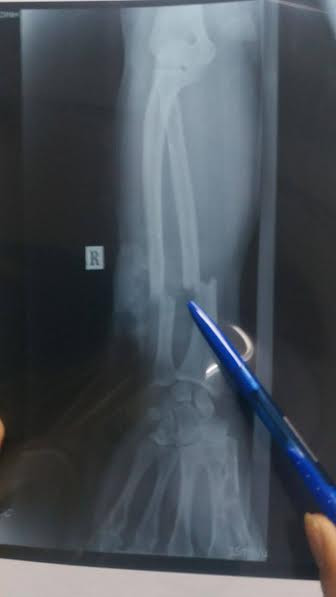

Theo đó, cánh tay của nạn nhân bị chém đứt lìa xương cẳng tay phải, cánh tay và cẳng tay chỉ còn dính với nhau bằng một phần thịt mềm rất nhỏ; bó mạch máu, thần kinh cẳng tay bị đứt phải thực hiện vi phẫu.

Cánh tay nạn nhân bị chém đứa lìa xương.